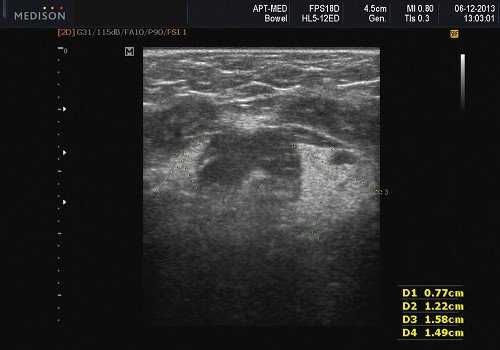

- Хронический склерозирующий сиаладенит. Гипоэхогенные, гетерогенные узлы фиброзное замещение паренхимы, двустороннее поражение

Хронический сиаладенит (ХСА) : хроническое воспаление ПЧЖ. Связан с состояниями, связанными с уменьшением выделения слюны, включая конкременты и застой слюны. Хронический склерозирующий сиаладенит (ХССА), опухоль Кюттнера. Опухолевидное состояние слюнных желез, при этом поднижнечелюстная железа поражается чаще околоушных желез. Часто имеется перидуктальный склероз, лимфоцитарная инфильтрация, уменьшение паренхимы секреторных желез, фиброз, ассоциированный сиалолитиаз (30-83%)

Хронический склерозирующий сиададенит. Гипоэхогенные, гетерогенные лимфоузлы / фиброз паренхимы, двустороннее поражение. Выступающие внутрижелезистые сосуды, проходящие через лимфоузлы без масс эффекта и их смещения